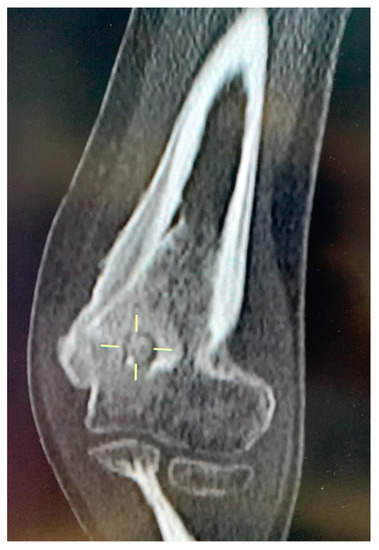

| 8 | F | 14 | right humerus, olecranon fossa, intra-articular cortical | pain, right elbow | yes | yes | yes | yes | yes | 9 | post-traumatic arthritis | CT-guided RFA |